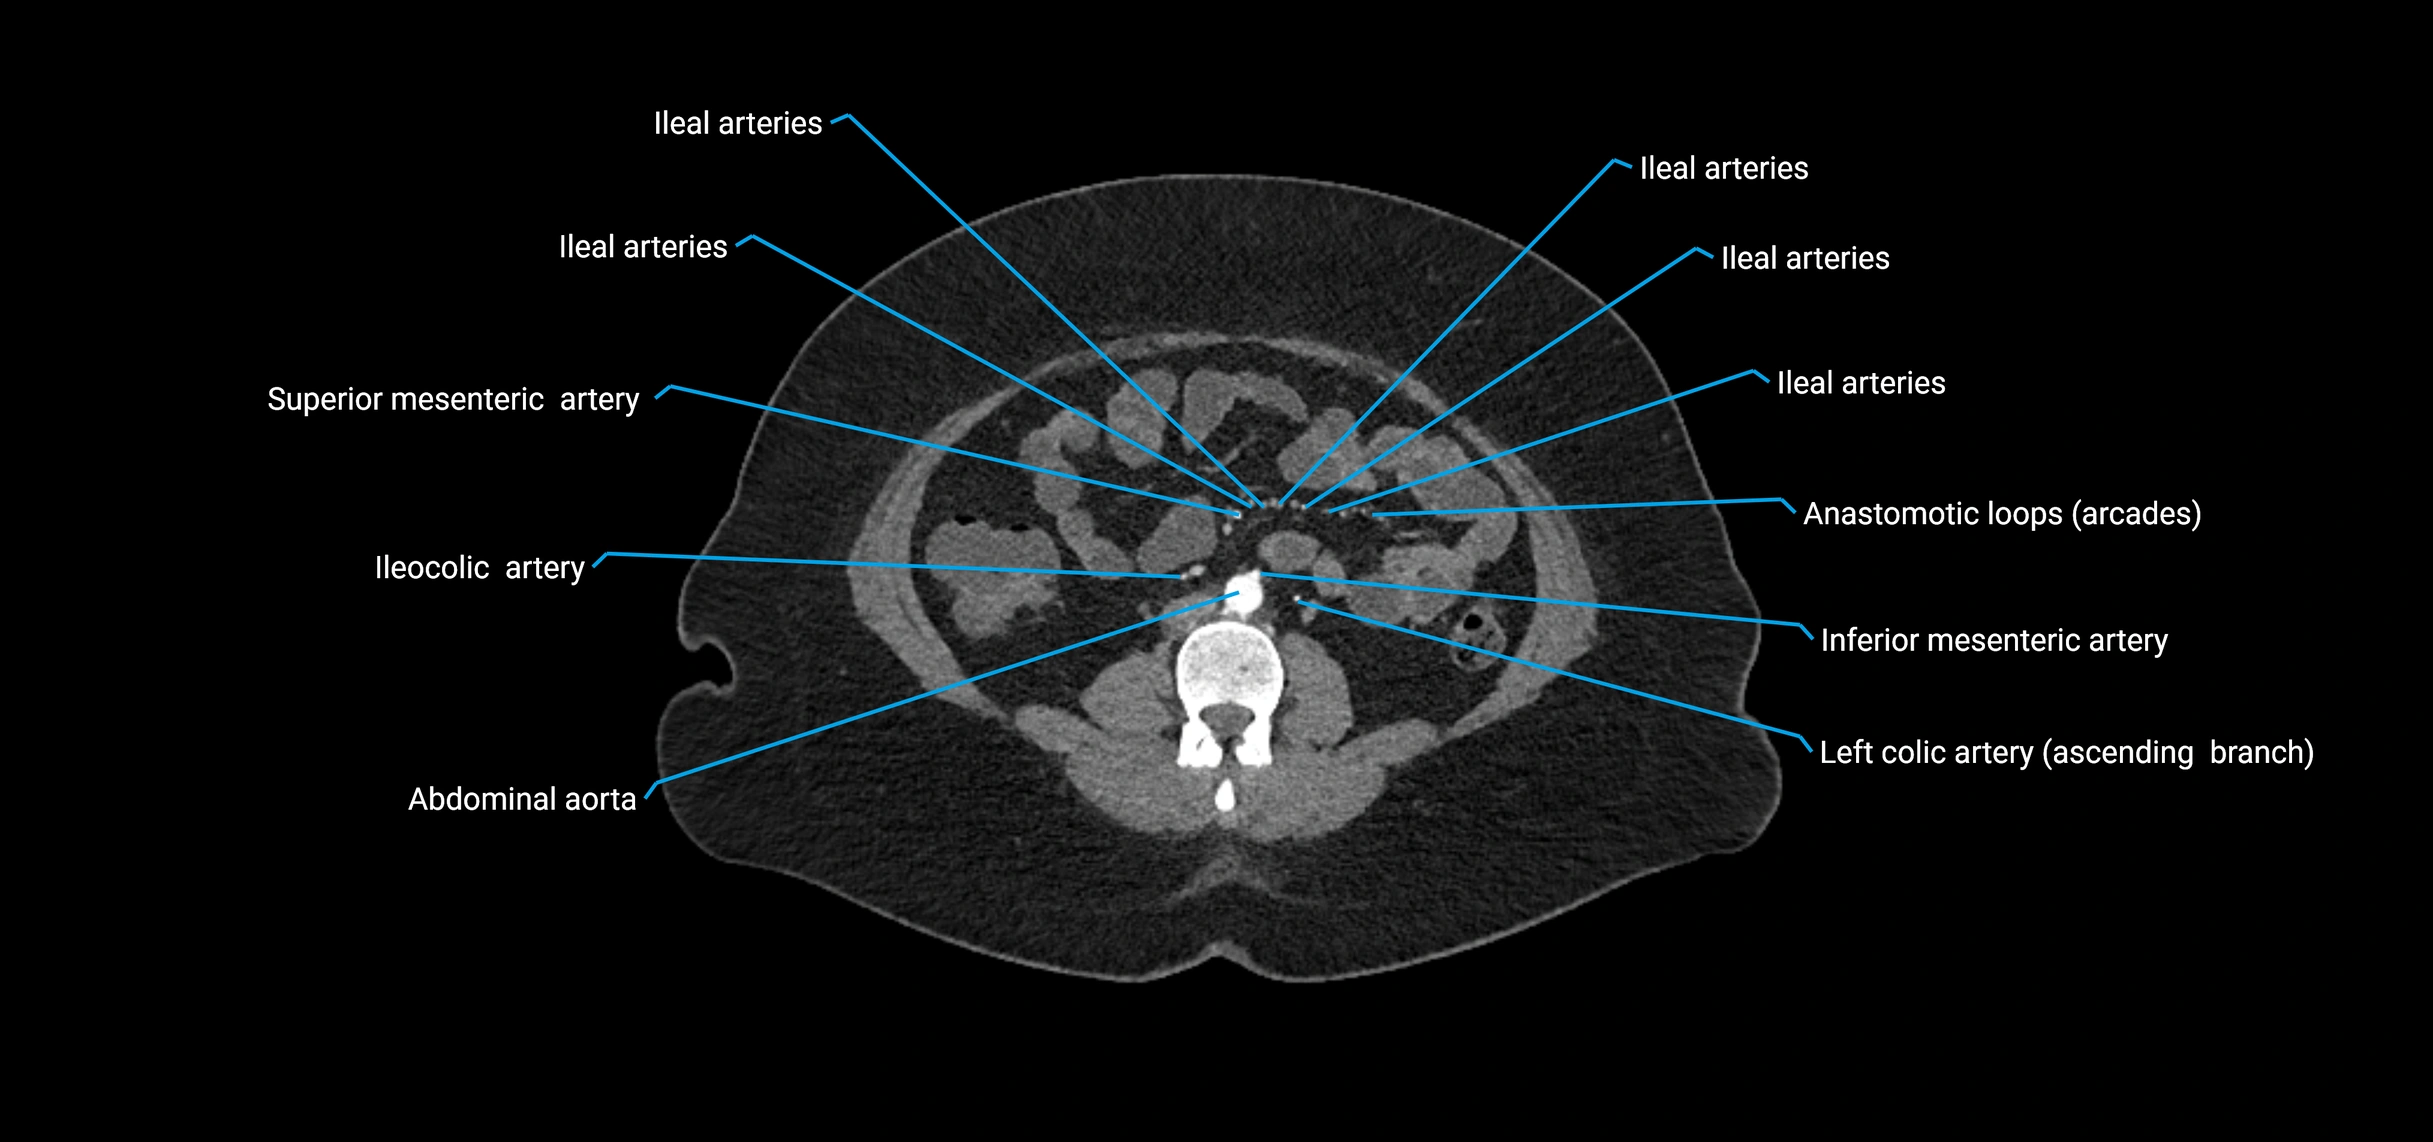

The abdominal aorta is the continuation of the thoracic aorta, beginning at the level of the aortic hiatus of the diaphragm (T12 vertebra) and terminating at the level of the L4 vertebra where it bifurcates into the right and left common iliac arteries. It lies slightly to the left of the midline and courses anterior to the vertebral bodies, surrounded by the retroperitoneal structures of the abdomen.

The abdominal aorta gives off numerous visceral and parietal branches, supplying the abdominal organs, pelvic structures, and lower limbs. It is the main conduit of oxygenated blood from the heart to the abdomen and lower body. The aorta is clinically significant as the common site of aneurysm, dissection, atherosclerosis, and traumatic injury.

Branches

• Unpaired visceral branches: celiac trunk, superior mesenteric artery (SMA), inferior mesenteric artery (IMA)

• Paired visceral branches: middle suprarenal arteries, renal arteries, gonadal arteries (testicular or ovarian)

• Parietal branches: inferior phrenic arteries, lumbar arteries, median sacral artery

• Terminal branches: right and left common iliac arteries

Contrast-enhanced CT (CTA):

• Gold standard for abdominal aortic imaging

• Provides excellent detail of lumen, wall, aneurysm, thrombus, and branch vessels

• Multiplanar and 3D reconstructions help in aneurysm measurement, stent graft planning, and dissection evaluation

• Detects acute rupture, traumatic injury, or occlusion with high sensitivity